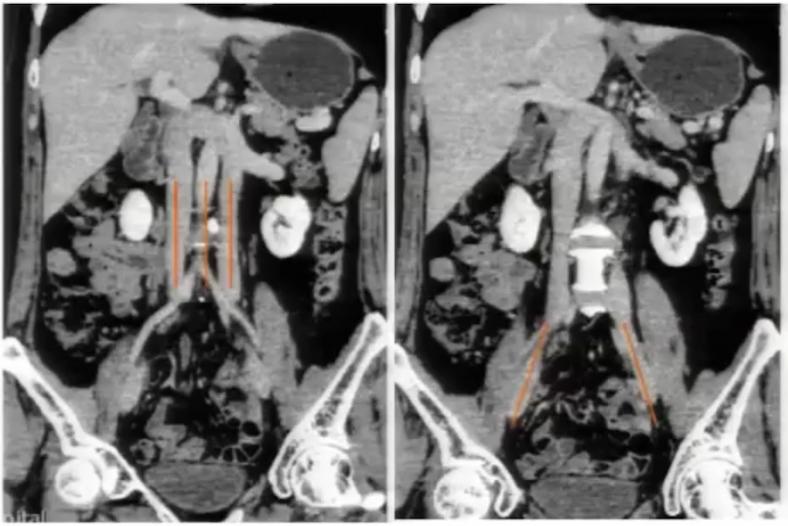

图2:冠状位重建显示下腔静脉肝段和肝下段缺如,向上直接延续为奇静脉

下腔静脉畸形

下腔静脉畸形 以双下腔静脉畸形及左下腔静脉畸形最常见。

左下腔静脉畸形为肾下段下腔静脉在主动脉的左侧上升,与左肾静脉汇合,通过主动脉前方与右肾静脉汇合,并在此水平上形成正常的右下腔静脉。

双下腔静脉畸形表现为左下腔静脉终止于左肾静脉,通过主动脉前方汇入右下腔静脉。

临床意义:

绝大多数情况无症状,不具有临床意义; 先天性下腔静脉畸形是引起特发性深静脉血栓的高危因素之一; 对涉及心脏、肝脏、肾脏及腰膜后的手术,可能会增加手术风险。

案例分享:

图11:腹主动脉两侧均有下腔静脉影,左侧下腔静脉向上与左肾静脉汇合后,在腹主动脉前方绕行,移行为右侧下腔静脉